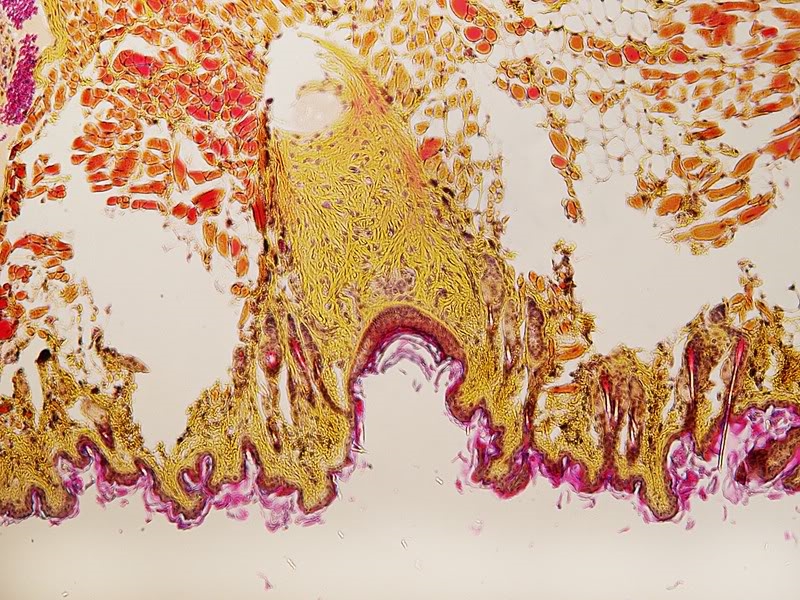

Bild 6: Haarfollikel mit einem tangentialen Anschnitt einer Talgdrüse.

Bild 7: Jörg hat absolut recht: Zahnanlage mit Zement und Schmelz (glaube ich - ist lange her, seit ich das zu letzten Mal gesehen habe..)

Bild 9: Zahnanlage, rechts Zement und links Schmelz (oder so)

Bild 10: Nochmal Zahn mit Thomes (?) -Fasern.

Bild 4 zeigt eine Tasthare wie schon erwähnt. Auf Englisch heißen sie "whiskers".

Sie entscheiden sich wesentlich von normalen Haare und das sieht Mann schon im Bild.

An die Unterseite von das blass Orange Wurzelgewebe ist ein Gelbe Nervenbundel zu sehen. Die purperen Erythrozyten (roten Blutkörperchen) gehören hier auch. Das ganze muss gut durchblutet sein und die vielen Nerven verspricht schon die feine Sensibilität.